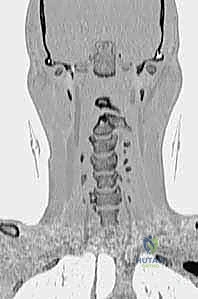

دقة التشخيص والتخطيط الجراحي قبل العملية

النجاح في غرفة العمليات يبدأ في غرفة الفحص. يتبع الأستاذ الدكتور محمد هطيف بروتوكولاً صارماً في التشخيص والتخطيط الجراحي.

- التصوير المقطعي المحوسب (CT Scan) ثلاثي الأبعاد: وهو الفحص الأهم لتخطيط الجراحة. يعطي الدكتور هطيف خريطة دقيقة لتشريح العظام، حجم الكتل المفصلية، ومسار الشريان الفقري، مما يسمح له باختيار حجم ومسار المسامير بدقة المليمتر.

الخطوة 6: تركيب القضبان واستعادة المحاذاة (Reduction)

بعد وضع المسامير الأربعة بنجاح، يتم تقييم وضعية الفقرات. إذا كانت C1 منزلقة للأمام، يتم استخدام أدوات خاصة لسحبها للخلف واستعادة المحاذاة الطبيعية مع C2 (عملية تُسمى Reduction). بمجرد تحقيق الوضعية المثالية، يتم قص قضيبين من التيتانيوم بالطول المناسب وتثبيتهما بقوة في رؤوس المسامير. هذا يخلق "سقالة" معدنية صلبة تمنع أي حركة بين الفقرتين.

الخطوة 7: التصوير الشعاعي داخل العمليات

طوال الإجراء، وخاصة بعد تركيب المسامير والقضبان، يتم استخدام جهاز الأشعة السينية المحمول (C-arm